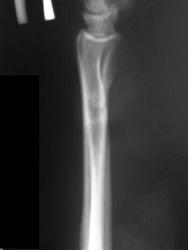

В связи с появлением и широкой популярностью шлифмашинок (в просторечии болгарки), травмы нанесенные этими прогрессивными агрегатами стали широко распространены. Характерной их особенностью являются переломы в виде линейных дефектов или ампутаций, чаще кистей-предплечий, стоп-голеней. Вот характерное наблюдение.

Вот еще, как по заказу сегодня случай попался

Все наоборот вставилось Недоволен первый снимок - через 1.5 мес после травмы, второй - исходный.

Очередной случай

Опять болгарка

Болгарочная травма предплечья

Еще предплечье, еще болгарка